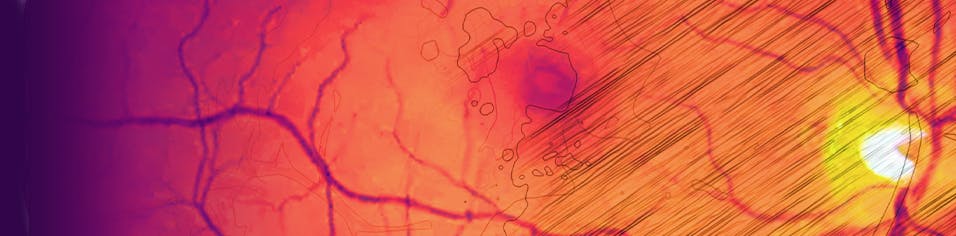

Case 3: PED, Metamorphopsia, and Wet AMD

By Nikolas J.S. London, MD, FACS

Patient History:

• 70-year-old white man who lives 4 hours from the office

• Patient presented with 20/40 VA OS. Significant, symptomatic metamorphopsia was noted, associated with a large pigment epithelial detachment (PED; Figure 1).

<p>Figure 1. The patient presented with 20/40 VA, metamorphopsia, and a PED.</p>

Click to view larger

Figure 1. The patient presented with 20/40 VA, metamorphopsia, and a PED.

Intervention:

• Monthly ranibizumab (Lucentis, Genentech) therapy was initiated. No significant changes were observed after four doses.

• At month 5, bevacizumab (Avastin, Genentech) was delivered. No change was observed after therapy.

• Aflibercept (Eylea, Regeneron) was administered during six monthly visits. No change was observed (Figure 2).

• After a discussion with the patient about treatment options, brolucizumab (Beovu, Novartis) therapy was initiated.

• After two monthly doses, the patient’s anatomy and metamorphopsia resolved, and VA was 20/30 (Figure 3). The patient was ecstatic about his vision and insisted on continuing brolucizumab therapy despite new safety concerns.

• For the past 6 months, the patient has visited the office every 8 weeks for brolucizumab therapy. Visual acuity and symptoms remain stable. However, he appears to be developing recurrent PED and subretinal fluid at the 8-week interval, and we will need to explore other options going forward. He has received seven injections of brolucizumab.

<p>Figure 2. After 11 monthly doses of various anti-VEGF agents, the patient’s condition remained largely unchanged.</p>

Figure 2. After 11 monthly doses of various anti-VEGF agents, the patient’s condition remained largely unchanged.

<p>Figure 3. After two injections of brolucizumab, the patient’s PED resolved, and VA improved to 20/30.</p>

Figure 3. After two injections of brolucizumab, the patient’s PED resolved, and VA improved to 20/30.